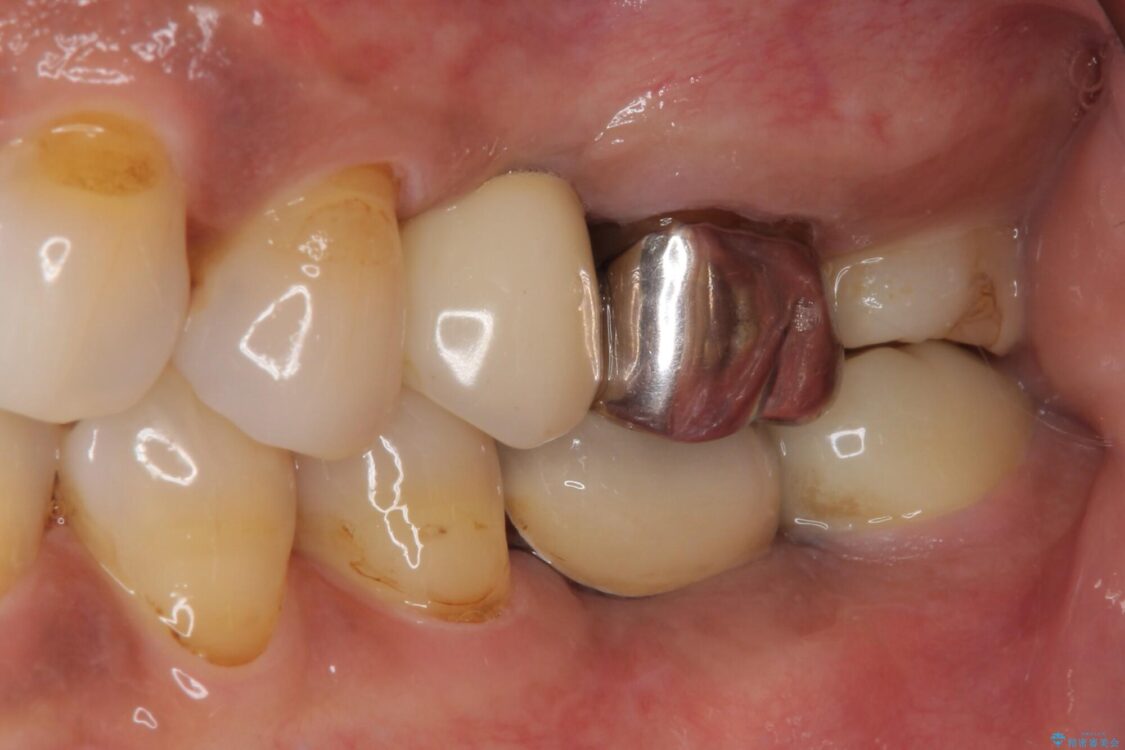

銀歯の装着されている奥歯がしみるとのことで来院された患者様です。

治療計画

銀歯周辺の歯が欠けており、むし歯も進行している状態であったので、オールセラミッククラウンにて補綴治療を行うこととしました。

治療前

• しみる奥歯 オールセラミッククラウンによる補綴治療 治療前画像